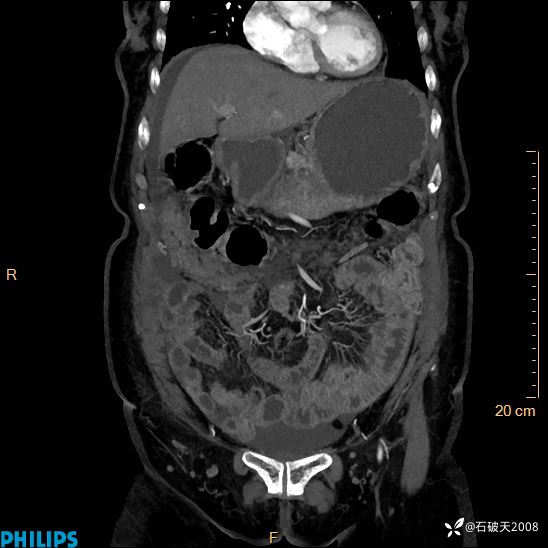

MIP